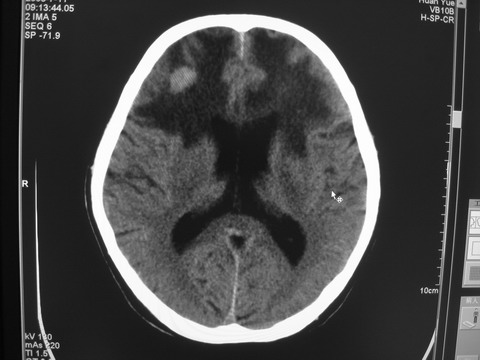

患者 男 69岁 头晕头痛不适

多发病灶,指状水肿,首先诊断转移瘤。

多个结节并周围大面积水肿区,多考虑多发性脑转移瘤

小病灶、大水肿,病灶多发,首先考虑多发转移瘤;建议查原发灶。

额顶叶多发小病灶、大水肿,首先考虑多发转移瘤;建议查原发灶

脑内多发病灶,小病灶,大水肿。

典型转移性肿瘤。

应进一步检查,查找原发病灶。

结果 : 该患者结肠癌病史5年 考虑脑转移